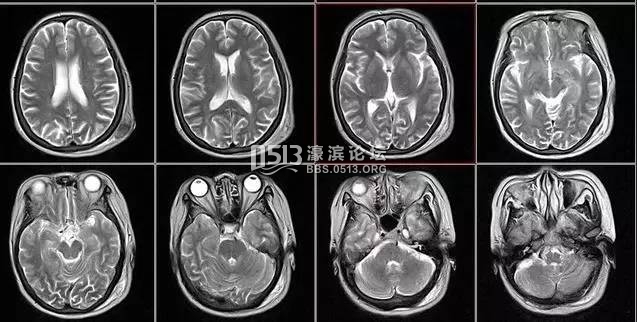

就诊时,医生常会开各种各样的影像学检查单:超声、CT、核磁……不少患者会质疑医生故意开高价检查单。其实,医生是依据不同病情选不同影像检查的。

2、颈椎腰椎——最佳选核磁、次选CT

颈椎病、腰椎间盘突出等椎间盘疾病需要观察椎间盘与相应的神经根,要想更好观察这些软组织,最优选择就是核磁。同样,对于关节、肌肉、脂肪组织检查,核磁也是首选。